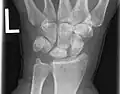

Left hand x-ray with Kienbock's Disease showing 4 mm negative ulnar variance and Kienbock's Disease Stage IIIB -